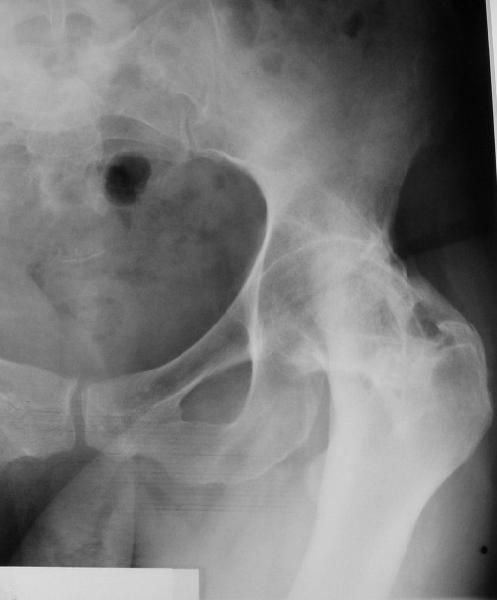

При обследовании выявлен анкилоз тазобедренного сустава в приведении.

Видимо, в период пребывания в тяжелом состоянии появились

гетеротопические оссификаты. За исключением того, что осталась одна

Корсет и анальгетики вряд ли решение. Первый вариант - удаление

оссификатов и эндпротезирование, второй - корригирующая остеотомия в

проксимальном отделе с устранением порочного положения.